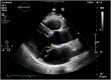

The association of mitral valve prolapse (MVP) with ventricular arrhythmias has long been known and has generally been considered a benign condition. In recent years, however, a small but not negligible risk of malignant ventricular arrhythmias and sudden cardiac death has been documented in the large population of subjects with MVP. The main predictors of major arrhythmic risk identified so far include history of syncope, ventricular repolarization abnormalities in the inferior-lateral electrocardiogram leads, right bundle branch block morphology of ventricular ectopic beats, finding of areas of myocardial fibrosis on cardiac magnetic resonance, and mitral annular disjunction (MAD) on echocardiogram, as well as a possible pro-arrhythmic genetic substrate. The stratification of arrhythmic risk, with the active search forred flags and in particular of MAD, is important to identify patients with the malignant arrhythmic variant of MVP in whom to implement closer surveillance and possible therapeutic interventions.